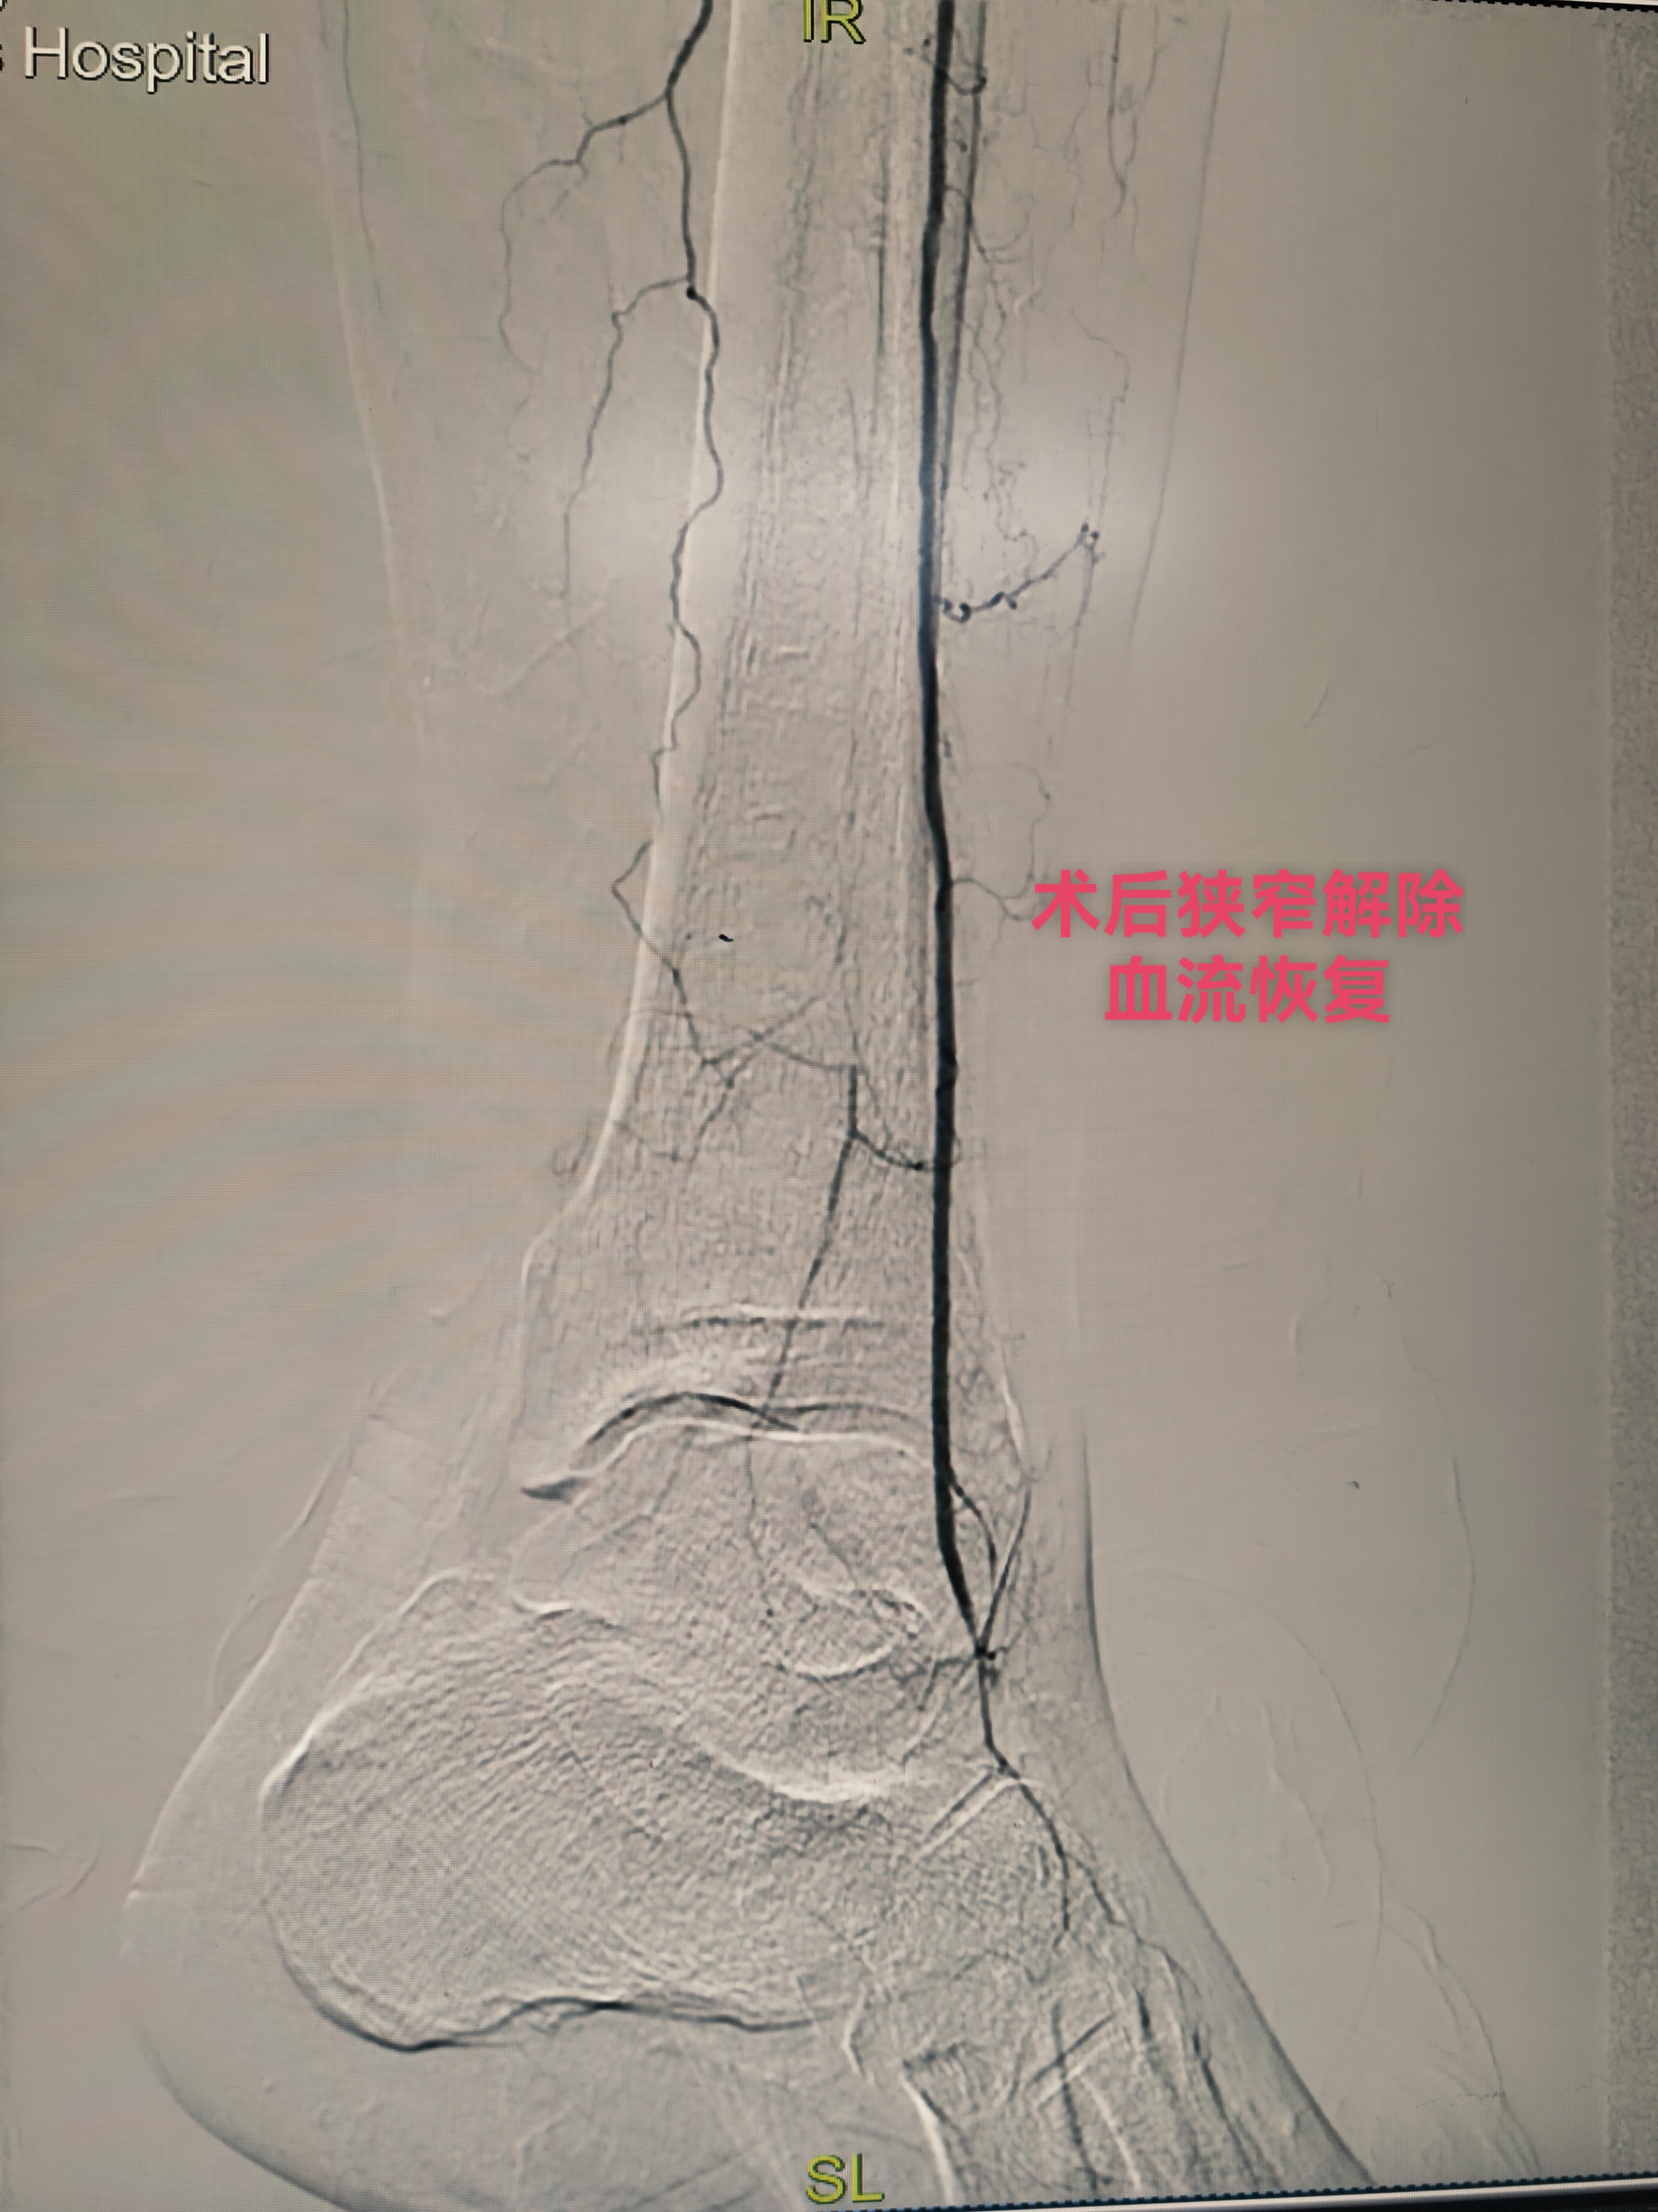

下午第一台糖尿病足三次腔内治疗再次未规律服药再次狭窄闭塞,下肢溃烂发黑,疼痛难忍。再次行球囊扩张术,术后皮温恢复,疼痛减轻。 第二台腮腺癌肝转移,经穿刺活检后证实后。行载药微球的灌注化疗栓塞。